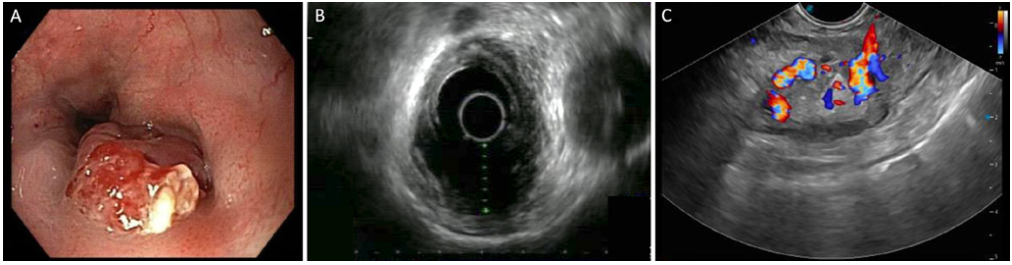

上消化道内镜检查发现大食管静脉曲张,距牙弓40cm处可见一大小20mm、外生性浸润性溃疡性病变(图1A)。内镜活检组织病理学检查结果尚无定论。

超声内镜提示病变质地不均、形态欠规则,边界不清,食管壁全层结构破坏(图1B、C)。

图1 (A)远端食管内镜表现:外生性溃疡性病变,周围环绕大食管静脉曲张。(B)超声内镜示病变质地不均、形态欠规则,边界不清,正常食管壁层结构完全消失;(C)可见多发粗大静脉曲张。